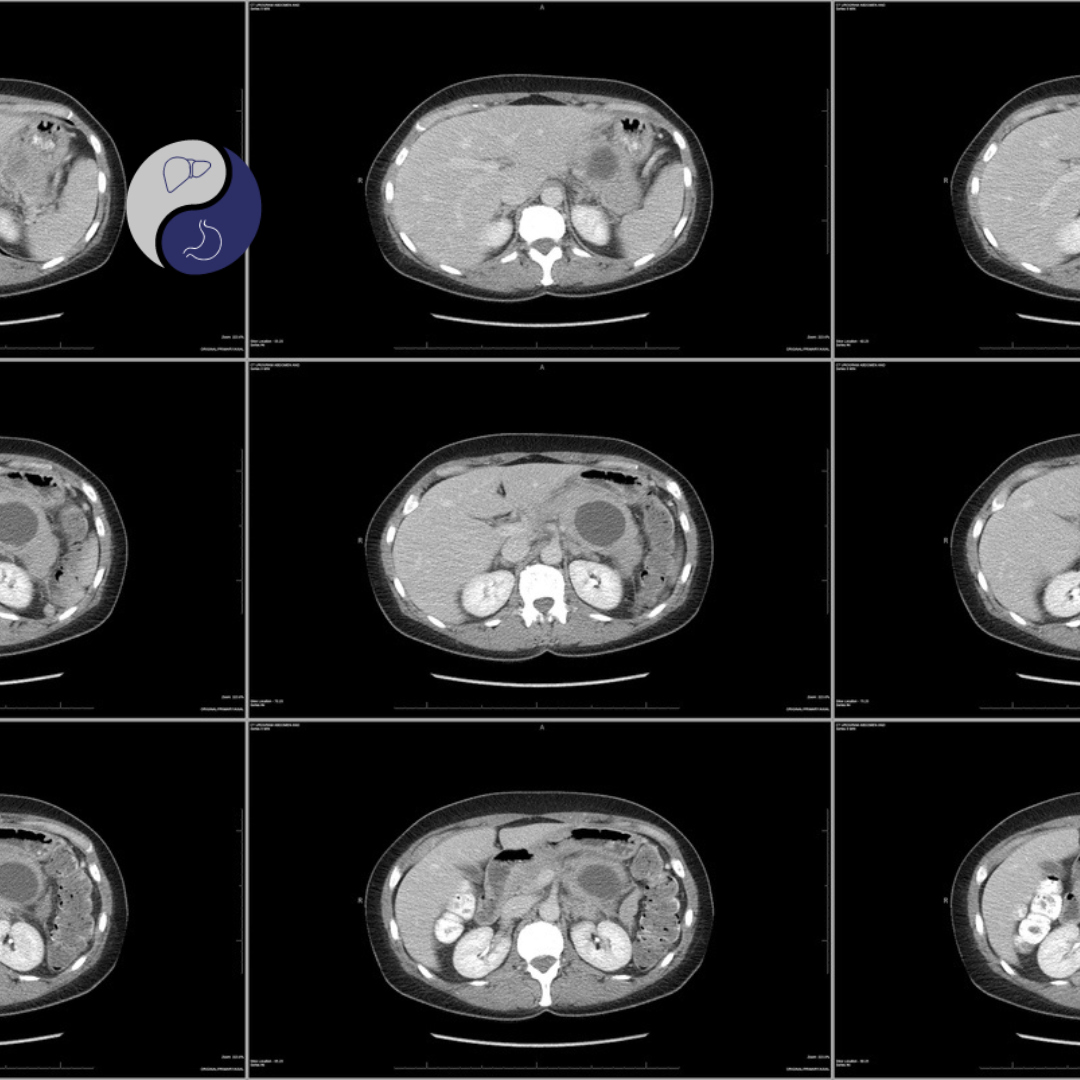

O mais importante é diferenciar o cisto seroso do mucinoso, pois este tem potencial de malignidade. O diagnóstico é feito por exame de imagem (tomografia ou ressonância, que é mais acurada), em que são vistas lesões císticas multiloculares, com aparência de colméia.

O diagnóstico é feito por exame de imagem, em geral é realizada a colangiorressonância e é importante diferenciar as lesões serosas. O cisto mucinoso se caracteriza por ser multiloculado (em geral com cistos maiores de 2cm), que podem ser separados e apresentar calcificações.